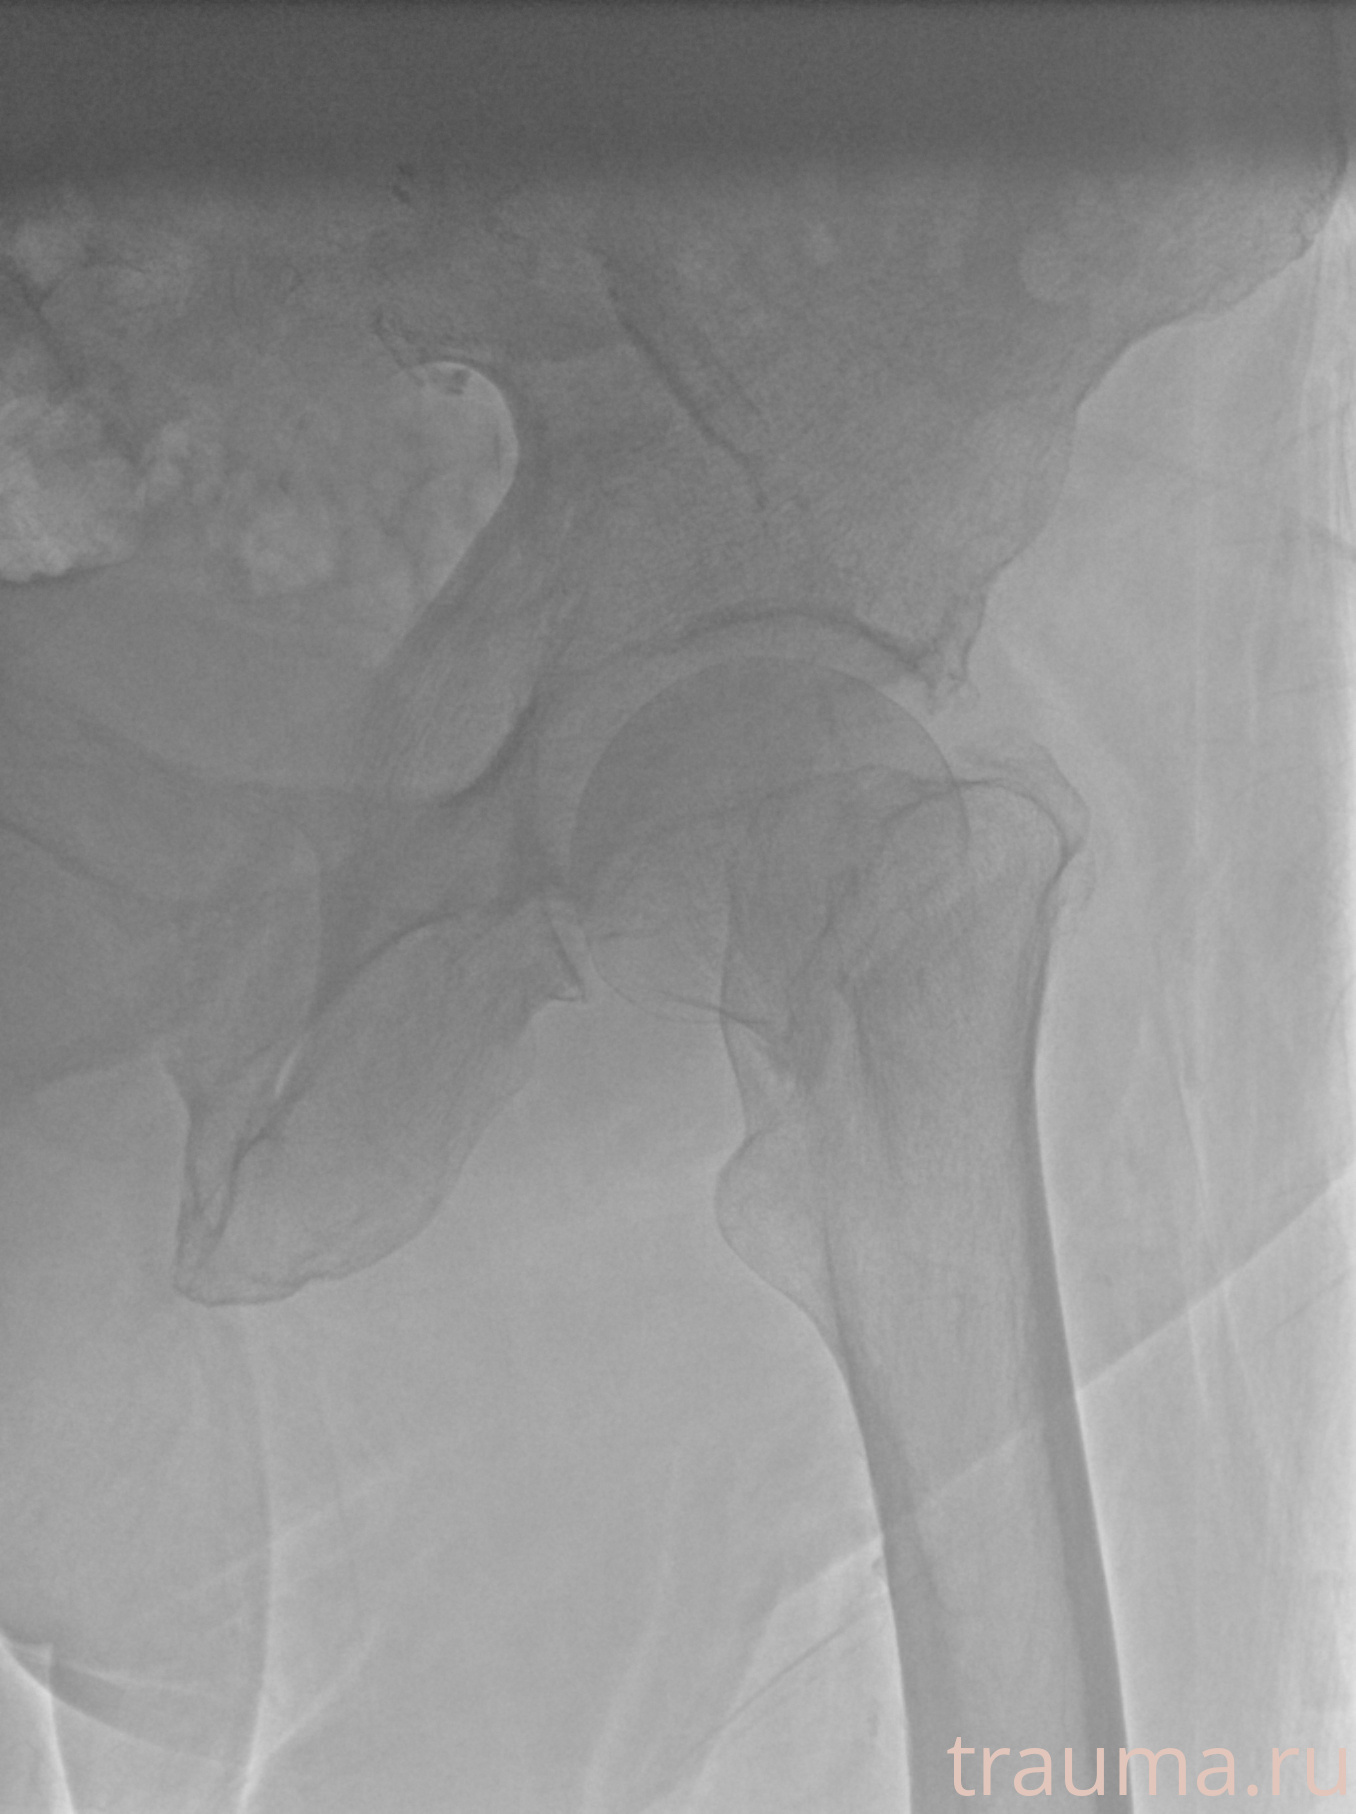

Рентгенограммы

Рентген на дому: по вашему адресу приезжает врач-рентгенолог, травматолог-ортопед с мобильным рентгеновским аппаратом, проводит диагностику травмы или заболевания, делает необходимые рентгенограммы, дает рекомендации по дальнейшему лечению. Получить качественные снимки в домашних условиях возможно благодаря уникальной методике, разработанной МосРентген Центром для института  Склифосовского